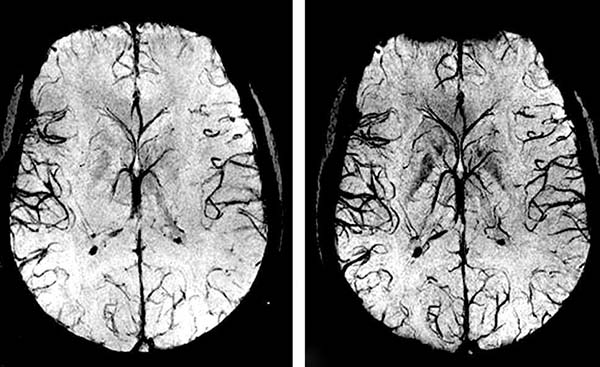

Przez 1,5 miesiąca przyjmowania Cardiotonus

przywracane jest krążenie krwi o 99,71%.

Krążenie krwi zostaje przywrócone systemowo – we

wszystkich naczyniach, tętnicach i naczyniach włosowatych.

Rozpuszcza blaszki miażdżycowe, skrzepy krwi i wapń. Zwiększa światło naczyń krwionośnych do 99,71% normy i przywraca krążenie krwi.